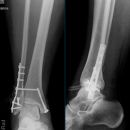

Sprunggelenk

Weber A

Es wurden keine Bilder gefunden.

Weber B

Weber C + dorsales Volkmann

Trimalleoläre

Vorderes Volkmann + lat. Talusschulter